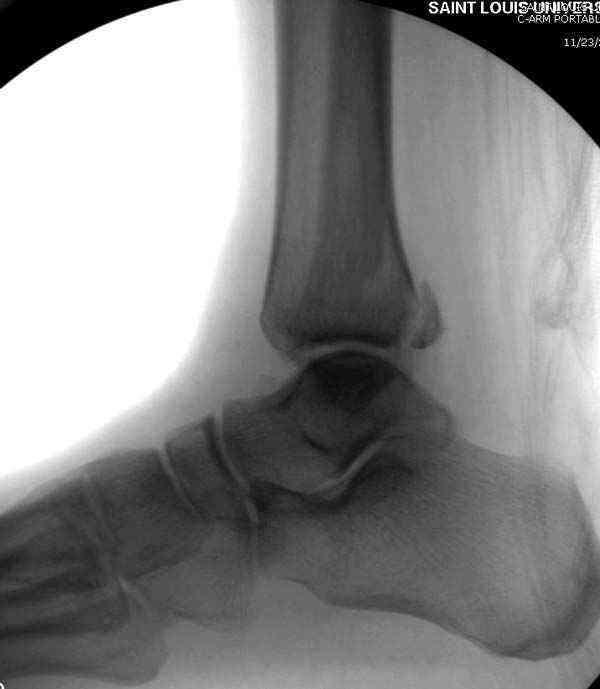

Здесь несколько частных случаев: перелом голеностопа со сравнительными снимками и разрыв синдесмоза, а также медиальная Hook пластина.

Нет первичных снимков, перелом очень низкий и под большим сомнением диагноз разрыва синдесмоза. Медиальная сторона отрепонирована на "хорошо" и, по-видимому, прорезание проволоки произошло во время операции. Без снимков трудно судить о высоте малоберцовой, а лодыжка находится в варусе. Лагирование получилось, но возле тонких шурупов передне-задний шуруп выглядит немного тяжеловато.

Во всех руководствах АО имеется описание техники применения низкопрофильных пластин 1/3 трубки, которые могут быть применены для фиксации наружной лодыжки. Фиксацию проводят кортикальными 3.5 мм шурупами, и если дистальная фиксация недостаточная, тогда усиливают конструкцию созданием hook plate. Сгибая конец пластины на последнем отверстии, внедряют его в дистальный отдел, и тем самым создается дополнительная фиксация.

Современные преконтурированные пластины не имеют таких недостатков, и разделяются на правые и левые, а также на латеральные и задние. Множественные дистальные шурупы 2.7 мм уменьшают подкожное раздражение, и такой имплант можно оставить на долгий срок без удаления.